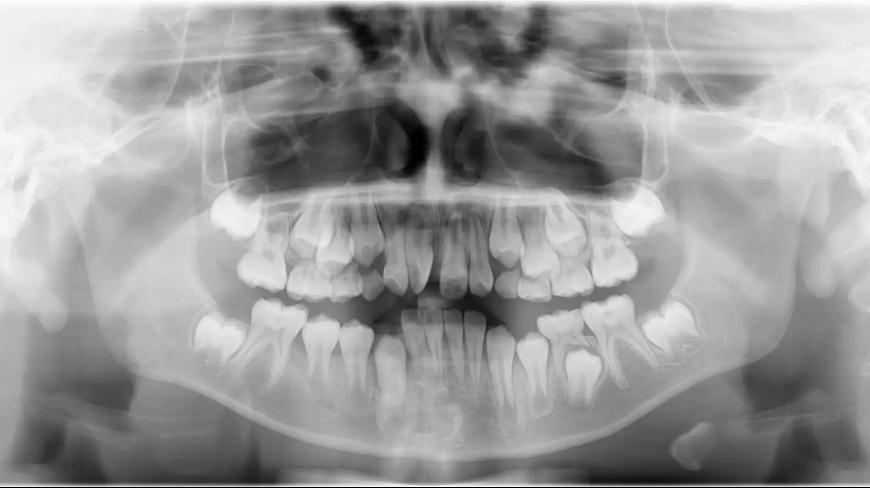

- Phát hiện và điều chỉnh các vấn đề phát triển hàm : Niềng răng sớm, thường từ 6 đến 8 tuổi, giúp bác sĩ chỉnh nha phát hiện và can thiệp kịp thời các vấn đề về sự phát triển của hàm và răng. Việc điều chỉnh sớm có thể giúp tránh các vấn đề nghiêm trọng hơn trong tương lai, như lệch lạc răng miệng, sai khớp cắn, hoặc các vấn đề về chức năng nhai.

- Điều chỉnh sự phát triển của xương hàm : Vào giai đoạn trẻ em đang trong quá trình phát triển, các xương hàm vẫn còn dẻo dai và có thể điều chỉnh dễ dàng hơn. Niềng răng sớm giúp tác động vào sự phát triển của hàm, giúp cho hàm trên và hàm dưới phát triển hài hòa, tránh tình trạng răng mọc lệch, vẩu hay móm sau này.

- Giúp răng mọc đúng vị trí : Khi niềng răng sớm, bác sĩ có thể tạo không gian cho các răng vĩnh viễn mọc đúng vị trí, giúp tránh việc phải nhổ răng vĩnh viễn sau này nếu răng mọc chen chúc quá nhiều.